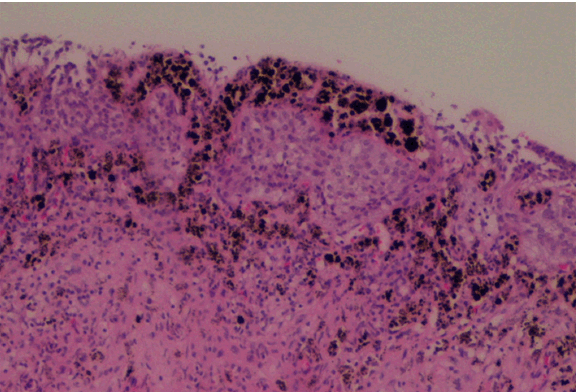

Bladder biopsy histologically revealed diffuse dark brown-black pigment mostly within the superficial lamina propria, focally in the overlying urothelium (Figure 4).

The pigment stained black by Masson-Fontana technique (Figure 5) with flat of punctuated patterns and disappeared after bleaching with potassium permanganate. There was not immunostaining for S100, HMB45 and Melan-A, indicating an absence of mucosal melanocytes. In conclusion, the histopathological result was compatible with primary bladder melanosis.

Figure 4: Diffuse dark brown-black pigment within the superficial lamina propria and focally involved the overlying urothelium (H&E stain, x100).

Figure 5: Staining of the granules is enhanced by Fontana-Masson stain.